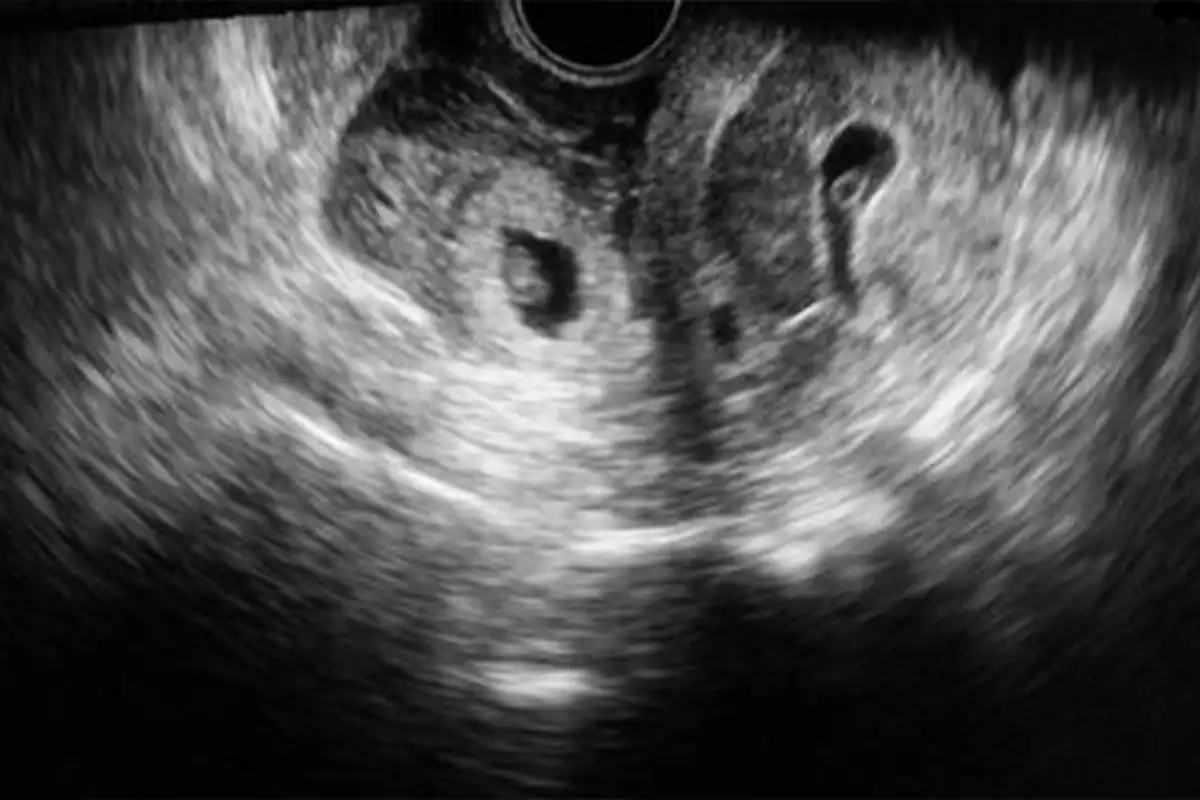

- Transvajinal Ultrasonografi: Rahim içinde ve dışında gebelik keselerinin varlığını gösterir.